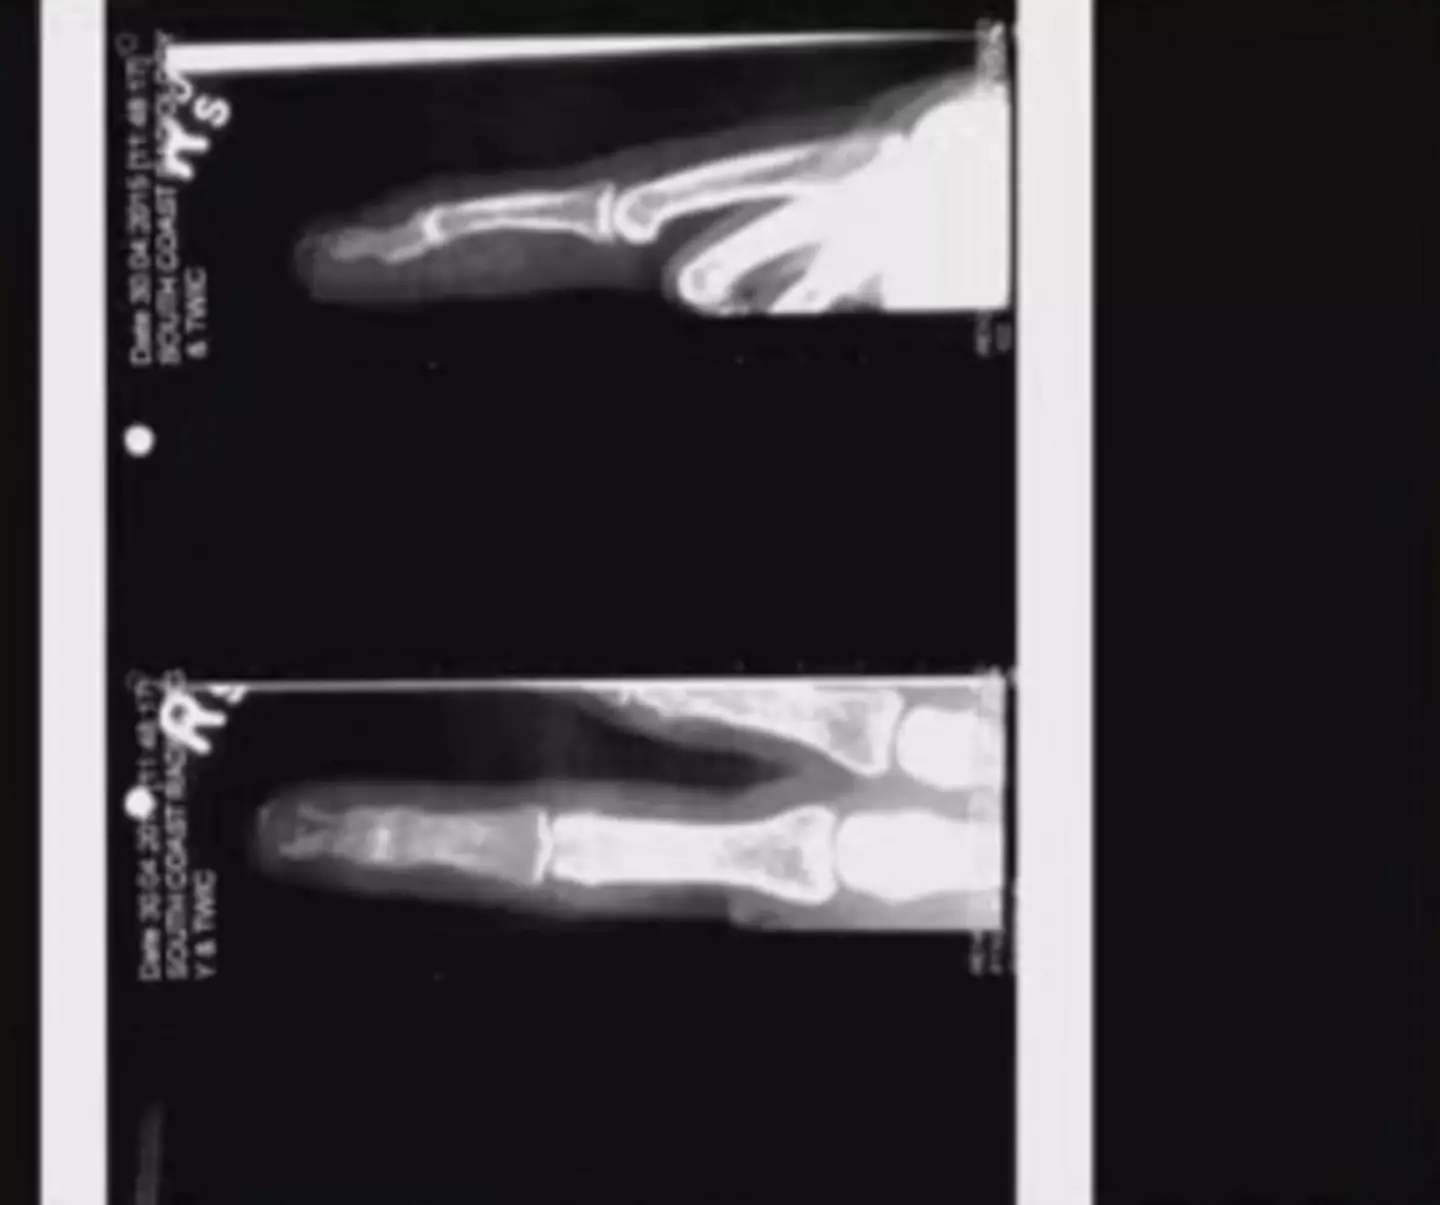

During the trial, one of the main talking points has been an incident that occurred in Australia back in 2015, when Depp lost part of one of his fingers.

Depp claims it was severed after Heard threw a vodka bottle at him, while her legal team are arguing that it was the Pirates of the Caribbean star who cut it off.

During his testimony, Moore claimed he did not believe Depp's story of how the injury was sustained made sense.

He said: "Well, the medical data is inconclusive. It’s not consistent with what we see in the described injury pattern or in the clinical photographs.

"Looking at the images, there’s really no significant injury of the dorsum of the finger and to create the type of injury with that type of a crush injury, we would anticipate both injury to the fingernail and other parts of the finger."